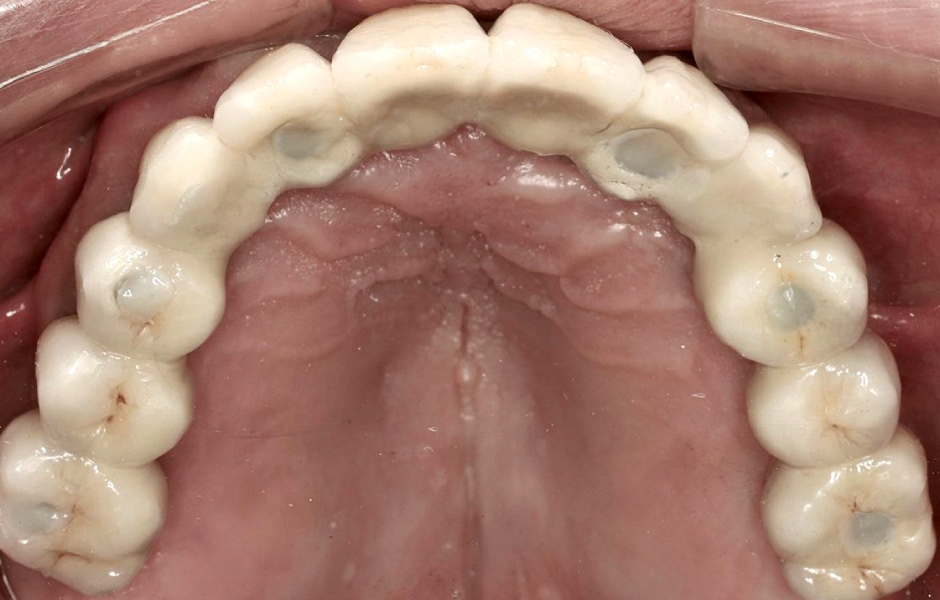

Definitivní náhrada byla nasazena a ověřena z hlediska estetiky, okluze a funkce (obr. 51–55). Panoramatický kontrolní snímek potvrdil, že všechny parametry protetického ošetření odpovídají očekávaným hodnotám (obr. 56).

Při kontrole po 18 měsících po dokončení ošetření bylo provedeno intraorální, extraorální a radiografické vyšetření. Nebyly zjištěny žádné patologické nálezy a výsledné parametry zůstaly stabilní (obr. 57–62).

Obr. 51

Obr. 52

Obr. 53

Obr. 54

Obr. 55